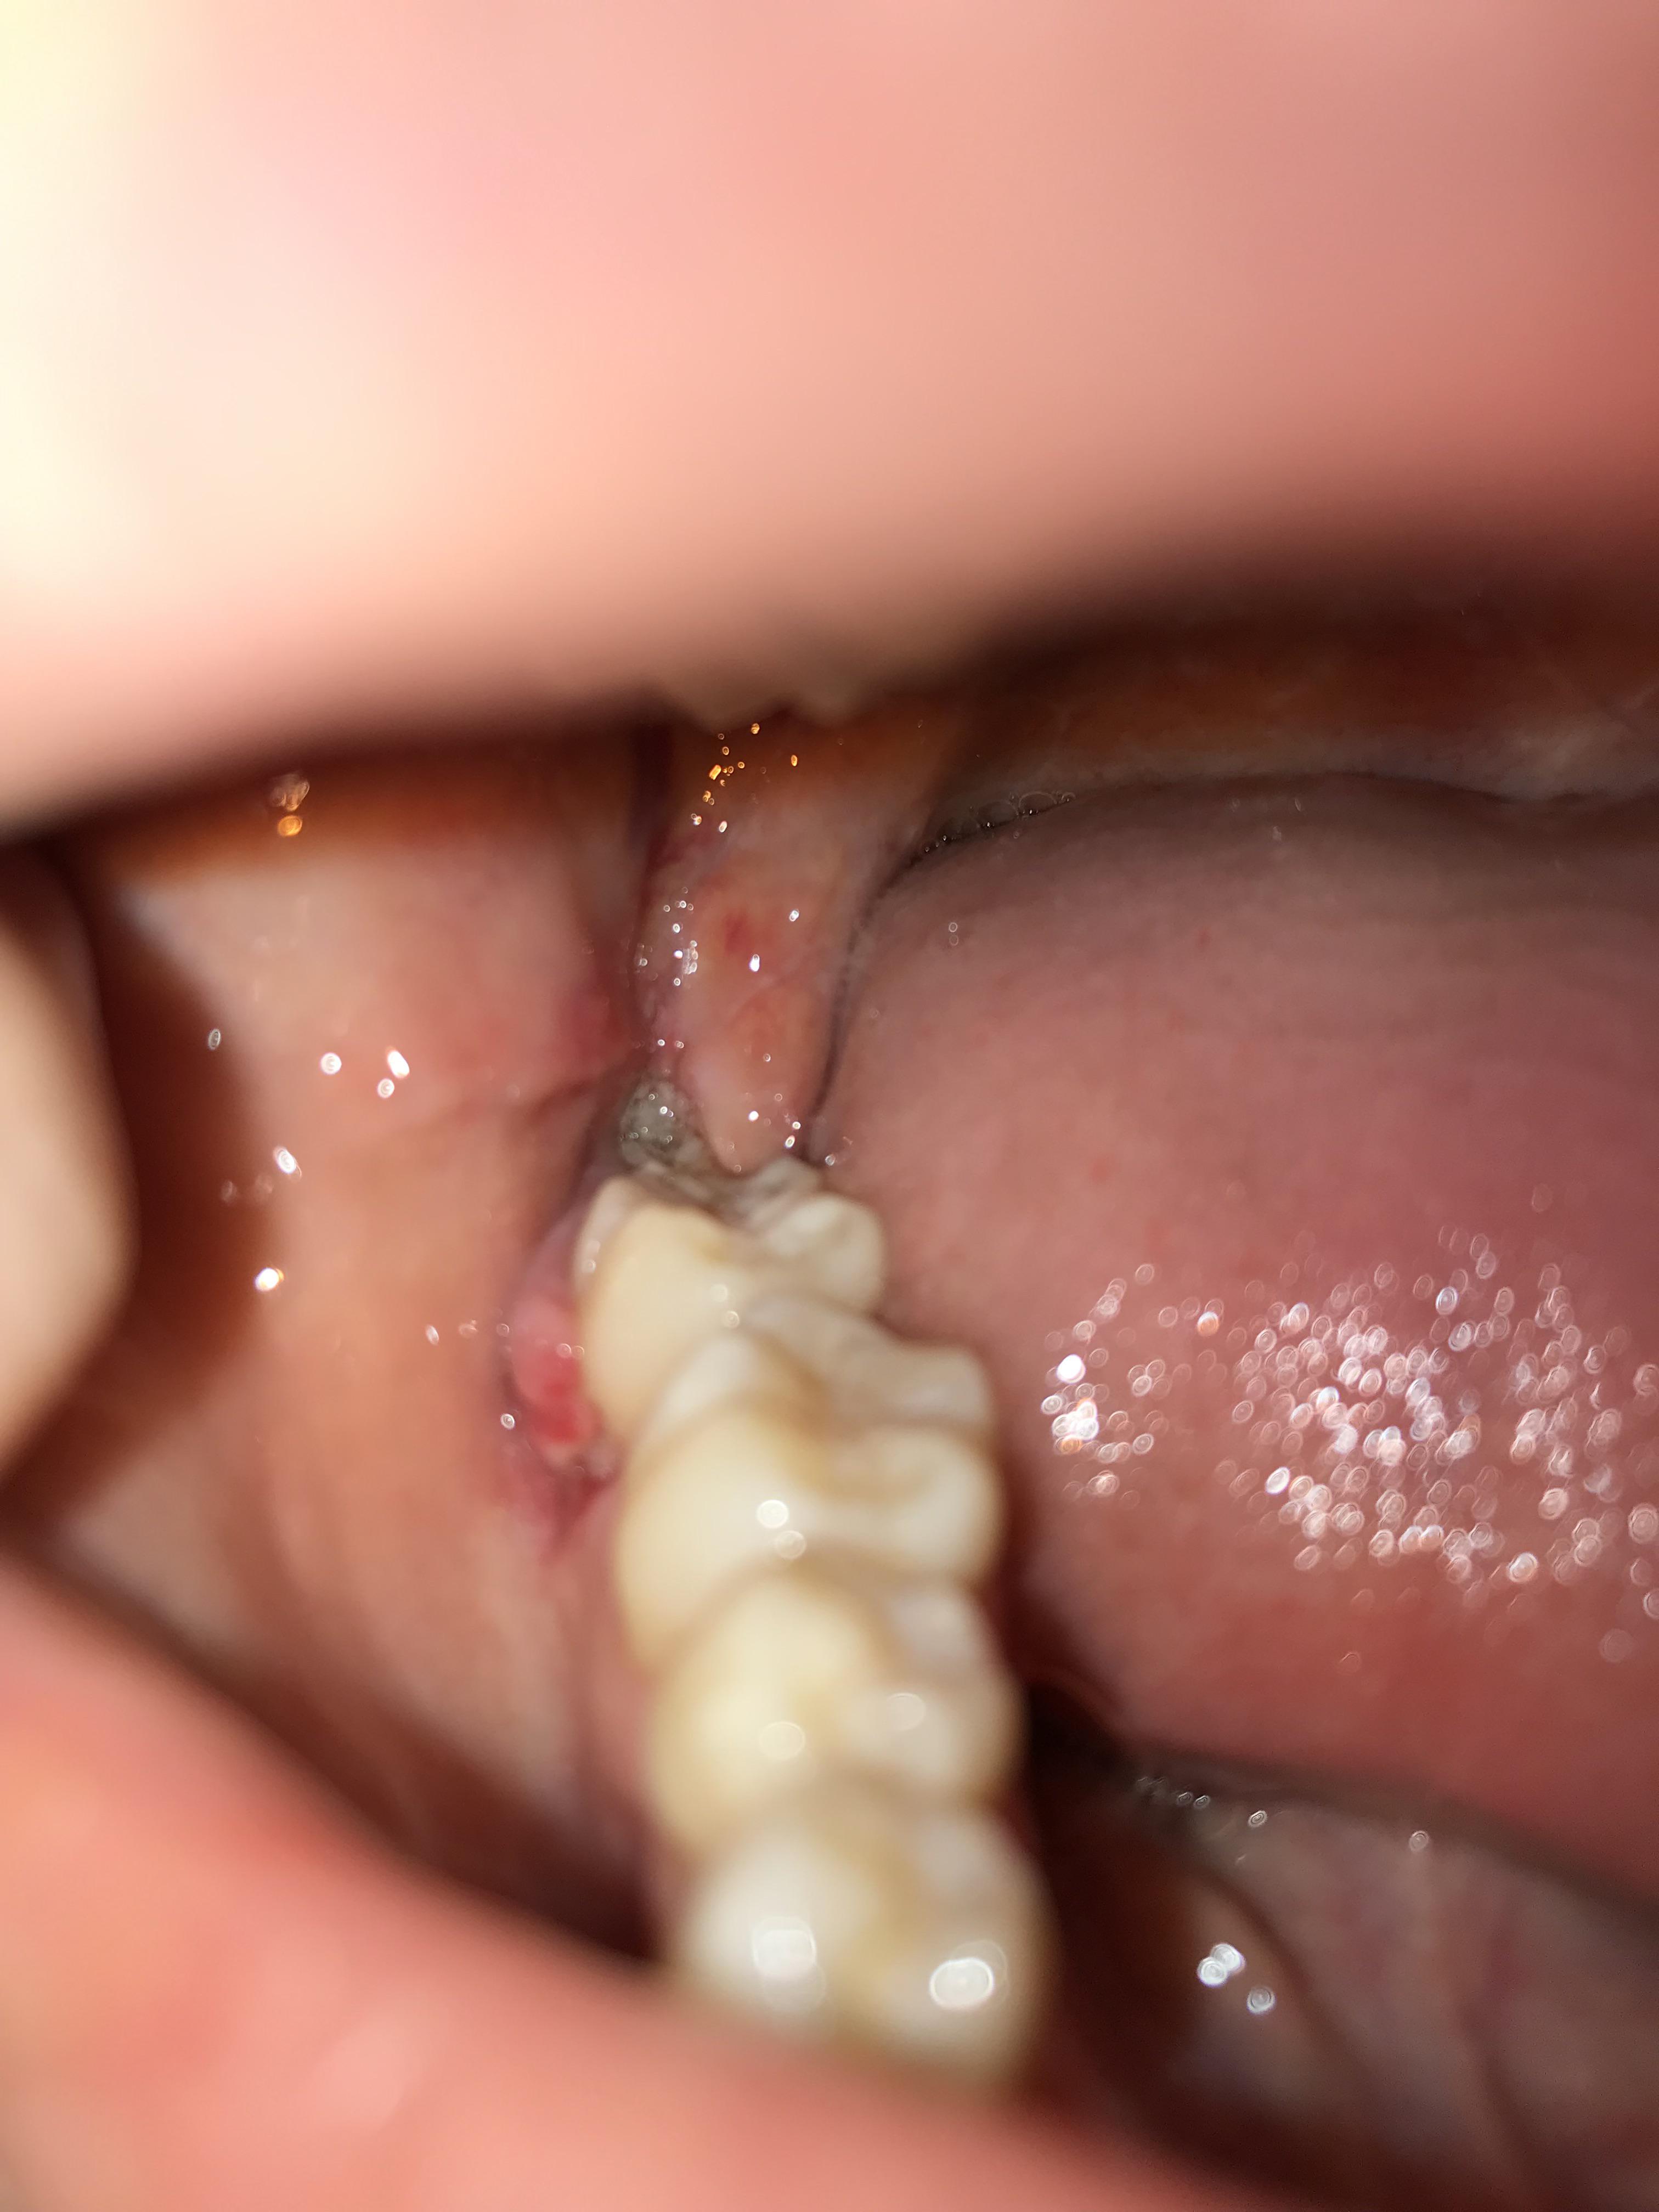

Stitches still in 15 days after surgery pain & irritation r/wisdomteeth Stitches Fell Out After Wisdom Tooth Extraction If you have dissolvable sutures, you’ll. The reason is because they leave behind multiple signs to let you know that they are no longer working hard at holding the gums together over the tooth socket. They keep the surgical site closed, promoting clot formation and. You'd be hard pressed to not know that your stitches placed after wisdom teeth removal. Stitches Fell Out After Wisdom Tooth Extraction.

Stitches came loose at wisdom tooth extraction site r/Dentistry Stitches Fell Out After Wisdom Tooth Extraction They keep the surgical site closed, promoting clot formation and. You'd be hard pressed to not know that your stitches placed after wisdom teeth removal came out. There are several reasons why wisdom teeth stitches might fall out early. Mine started coming out on day 3 you’ll have a hole. | what should you do? After a dental extraction, stitches. Stitches Fell Out After Wisdom Tooth Extraction.